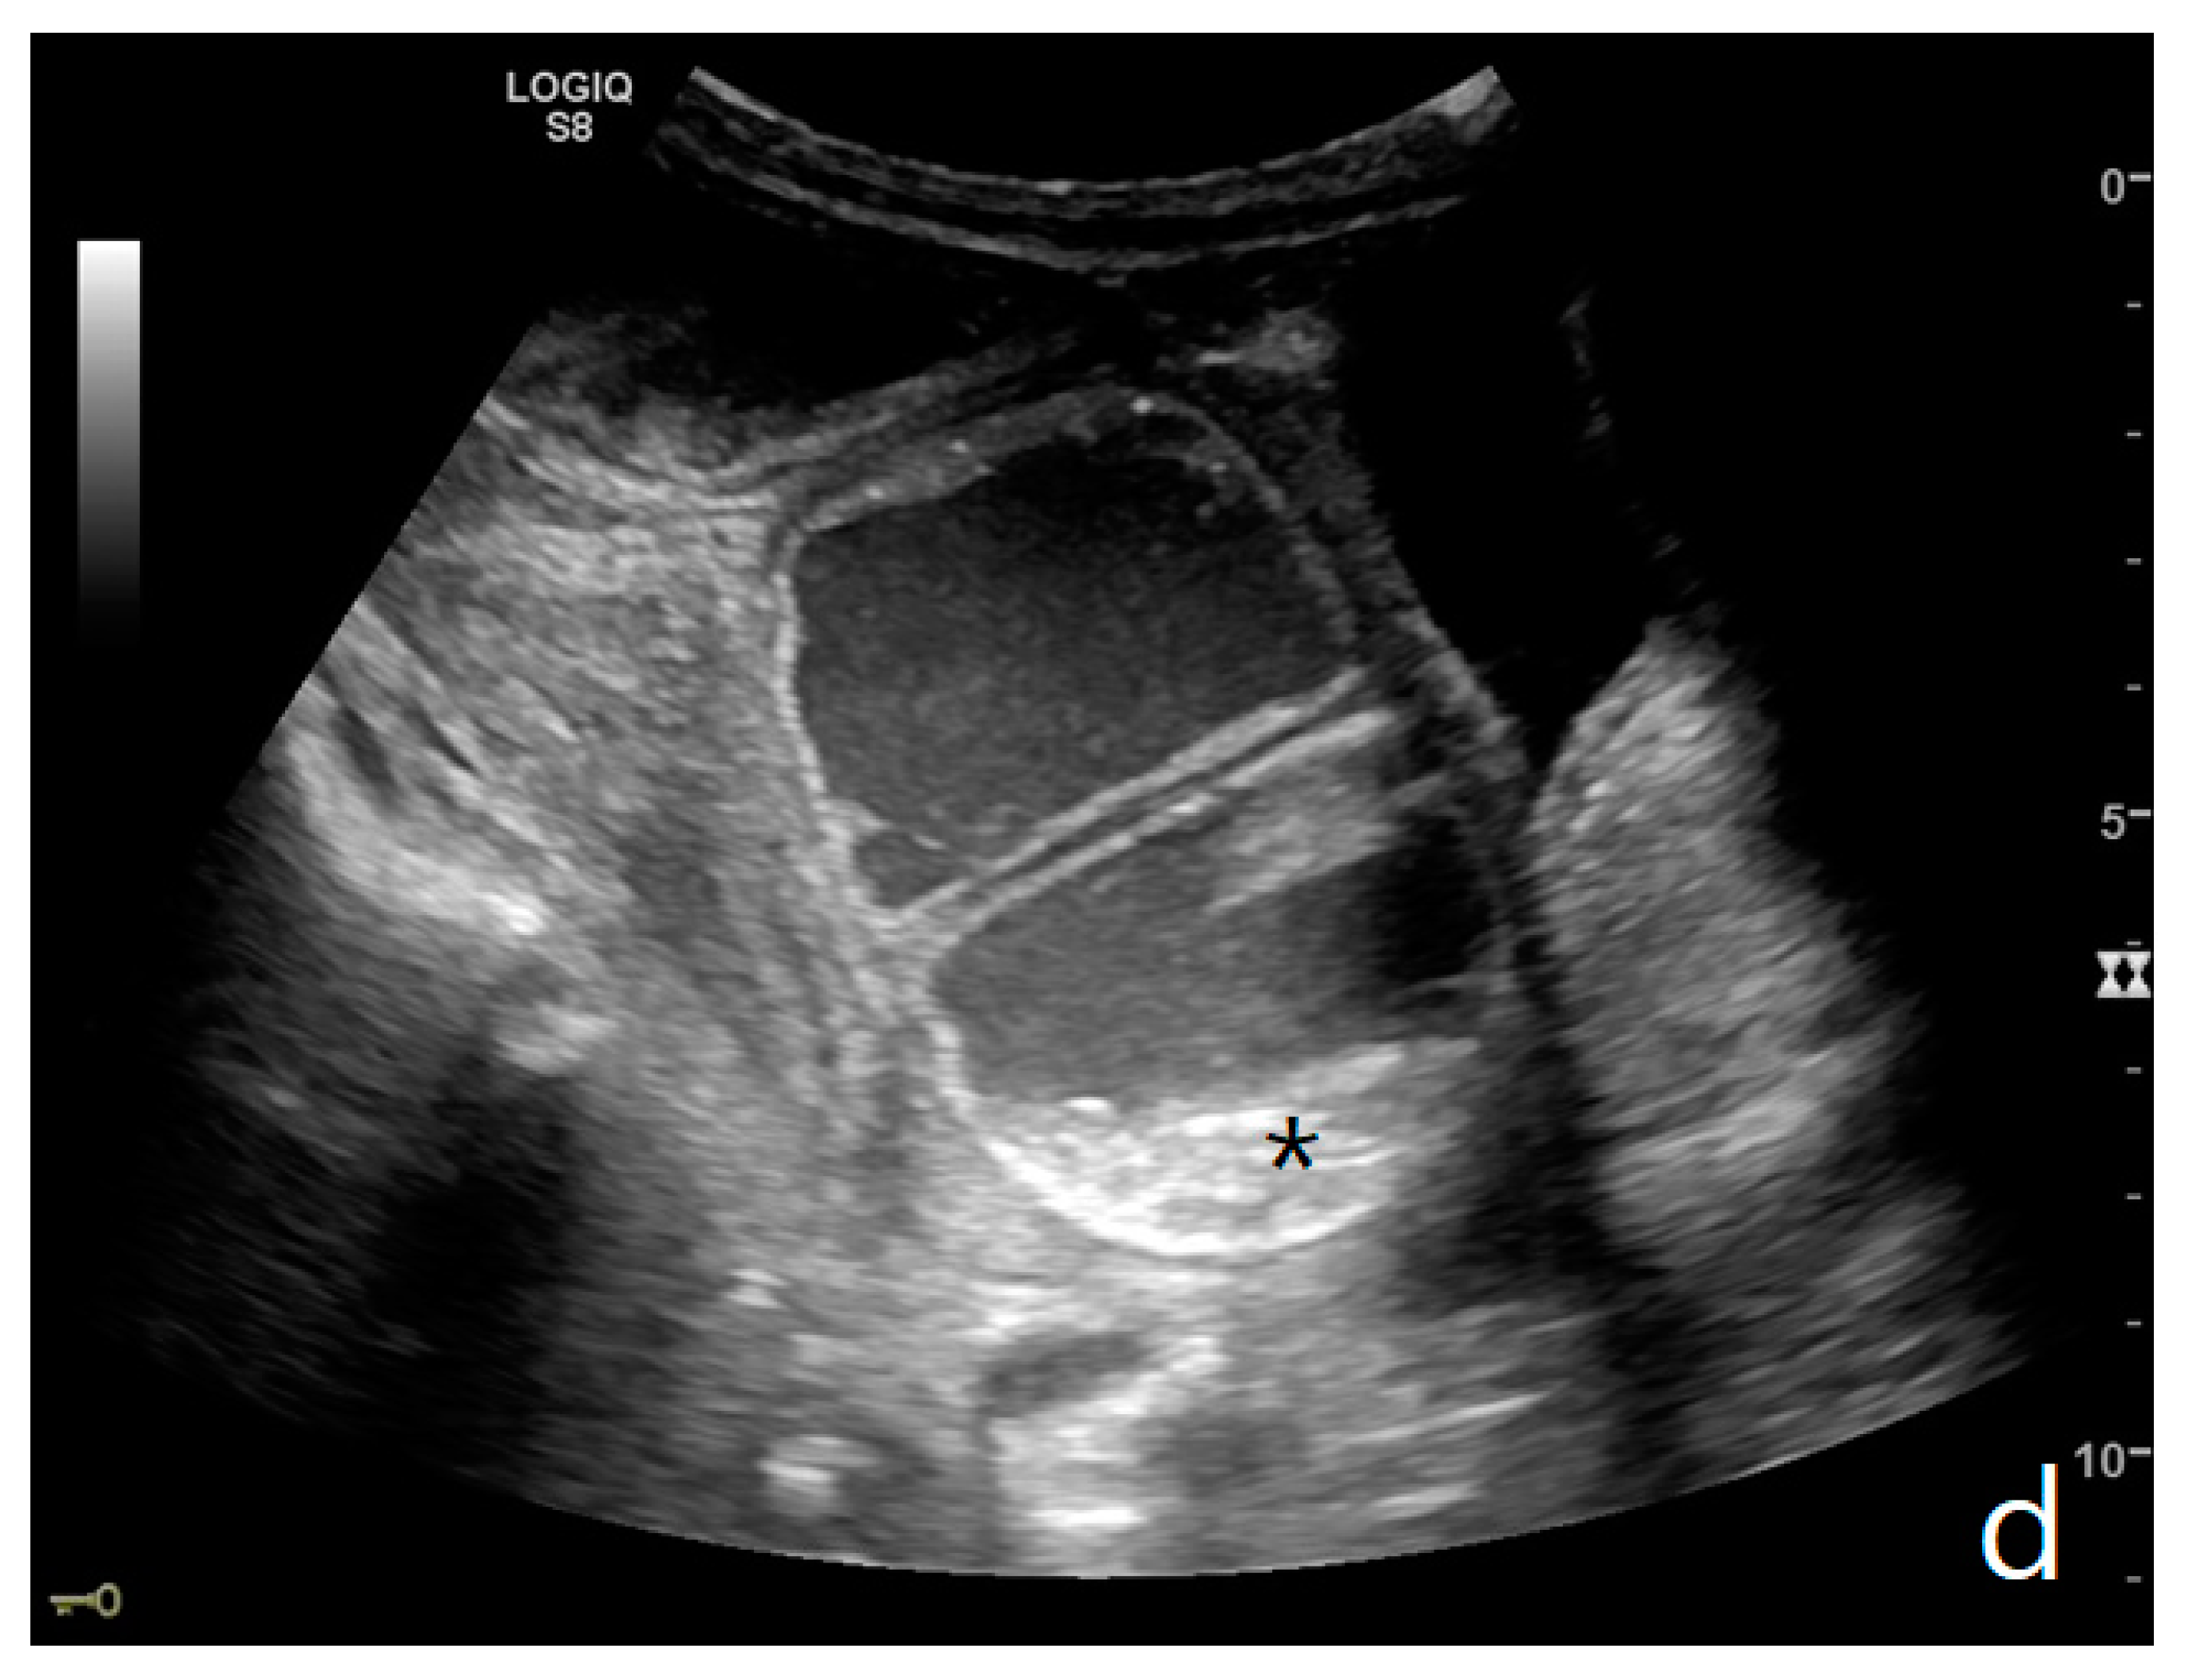

Figure 3.

A decompensated SBO, presenting fluid-filled, dilated small bowel loops with increased parietal thickening (*) (a) and free fluid between bowel loops (a). ‘Caliber jump’: a difference in caliber between the swollen loops upstream (white arrows) (a,b) and the collapsed loops downstream of the obstruction (black arrows) (a,b).